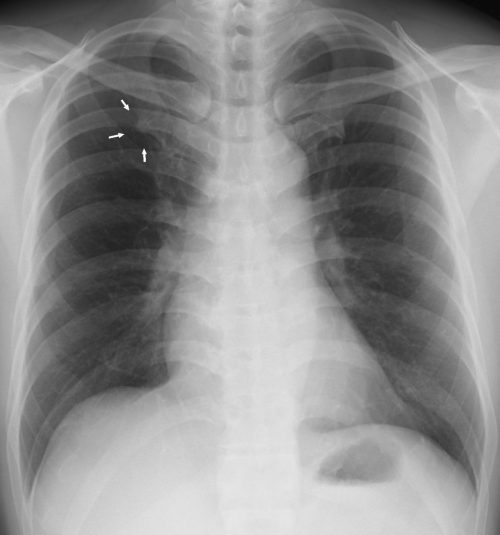

G.陳旧性結核(多発の孤立陰影、石灰化陰影) ①線量・体位ともに良好にみえるが、肺野が黒すぎて肺紋理がはっきりせず、レントゲン線量がやや過多な印象。

②右の側胸部肋骨の配列が内側に凹になっていて胸郭の変形と、同時に肋骨の骨量が薄く骨粗しょう症を思わせる。

③縦隔はやや拡張していて、大動脈弓に沿うように石灰化陰影、同時に大動脈の拡張と右心辺縁に円形の周囲が石灰化した陰影をみとめる。左心陰影に隠れてやはり不規則な2~3ヶの石灰化陰影がみられる。一部は肋軟骨の石灰化。(骨より白く見えるときは石灰化していると考えるのが妥当)

④右横隔膜は鮮明だが、左はぼやけた印象があり胃の陰影と重なって4~5ヶの小さい石灰化陰影をみとめる。左の横隔膜肋骨角はやや不鮮明。

⑤右肺上肺野には6~7ヶの大小不同の石灰化陰影があり、中肺野外側肋骨に沿ってまた下肺野大きな円形の辺縁が石灰化した陰影の横に、不規則な形状の石灰化した孤立陰影、肋軟骨部の石灰化をみとめる。

⑥左肺には上・中肺野に小陰影をみとめる他に、中肺野にうねった不規則な線状の陰影があり上葉と中葉の葉間の石灰化陰影を思わせる。

[評価] 空洞周囲が石灰化した陰影(乾酪巣の周囲の石灰化)、葉間の石灰化を思わせる陰影、肺野の散在する陰影等から結核が陳旧化したものと考えられる。同時に大動脈瘤、骨粗鬆症の存在が推察される。